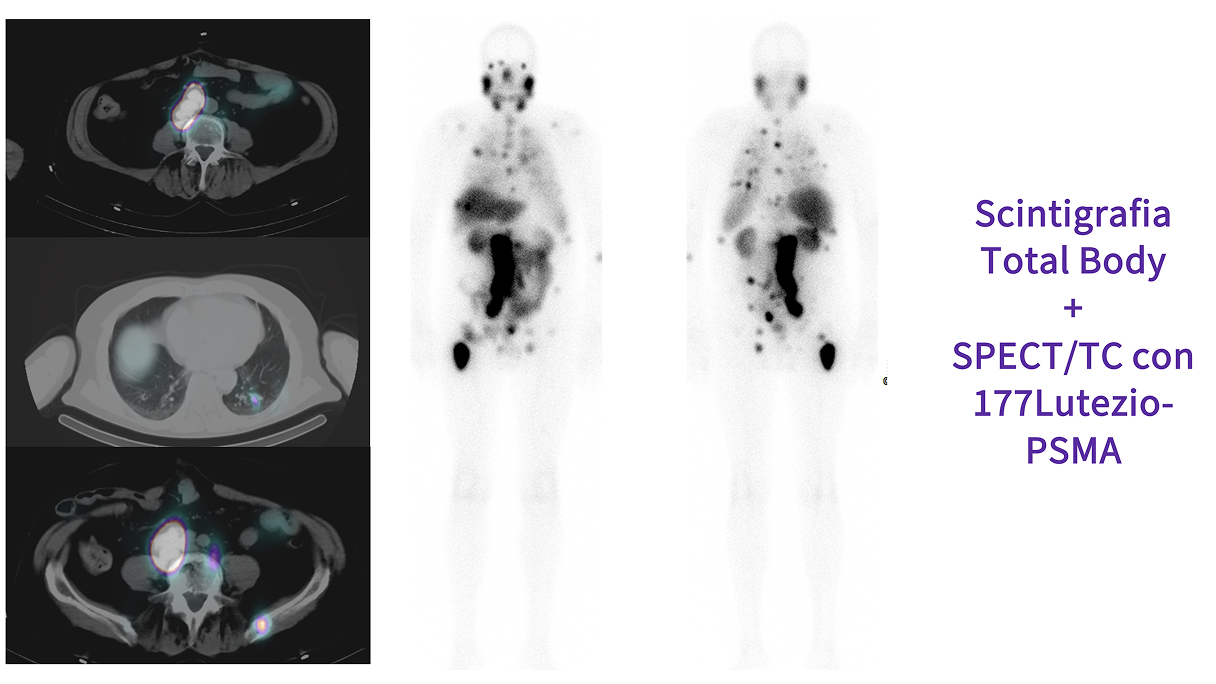

Caso condiviso da Saima Mushtaq

Paziente con anamnesi di malattia coronarica e pregresso impianto di stent sulla discendente anteriore sinistra.

Per prima cosa, esamina l'intera scansione. Concentrati sul tronco comune e sulla porzione prossimale della discendente anteriore sinistra.